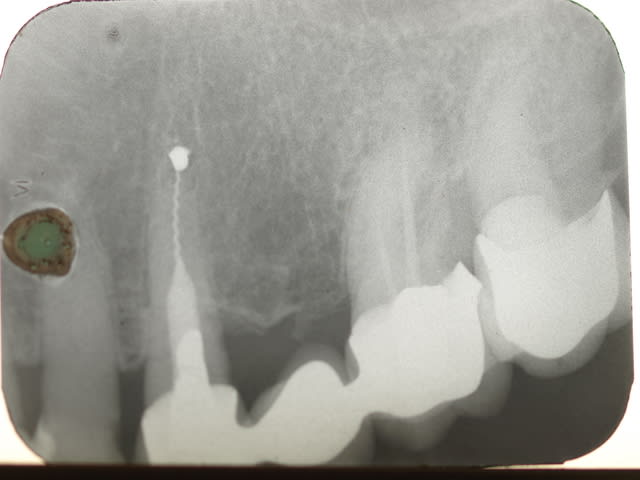

Euh .......les gas y a pas un truc qui vous gêne là ? Vous avez vu les radios ?

Premièrement il faudra que m'expliquer comment le bridge qui au départ est infiltré voir carié sur la 4 se retrouve comme par magie ré-adapté.

Le tenon n'est pas le même

Le traitement endo n'est pas le même

La 7 est couronnée (cantilever) sur une radio , pas sur la radio pré-op

Le niveau osseux n'est pas le meme sur les 2 radios

BREF IL NE S'AGIT PAS DU MEME PATIENT....

Tu dis avoir démonté le bridge et reposé tel quel , ce qui est faux au vu de la radio pré-op en page 5..... le tenon , ete le trt endo sont différents .

Tu as donc inventé une technique pour réadapter des prothèses non adaptées ....... le hyatus a disparu comme par magie , donc 2 possibilités :

- Tu as refait le bridge et tu ne le dis pas

- La radio pré-op est de quelqu'un d'autre

Les autres radios je m'en fous , je dis juste qu'entre les deux radios (15 ans) il y a du y avoir une intervention divine ....

Je te trouve bien hargneux sur ce bridge, parce que si tu regardes bien les radios tu vois bien que c'est le même patient quand-même, et que la 7 a été couronnées par la suite. Les radios ont une incidence un peu différente.

Si 15 ans sépare la radio pré opératoire de la dernière radio, force et de constater que la réimplantation a fonctionné.

Je note néanmoins une cratérisation apparue autour de la partie cervicale de la racine réimplanté, suite à l'intervention, mais stabilisée par la suite.